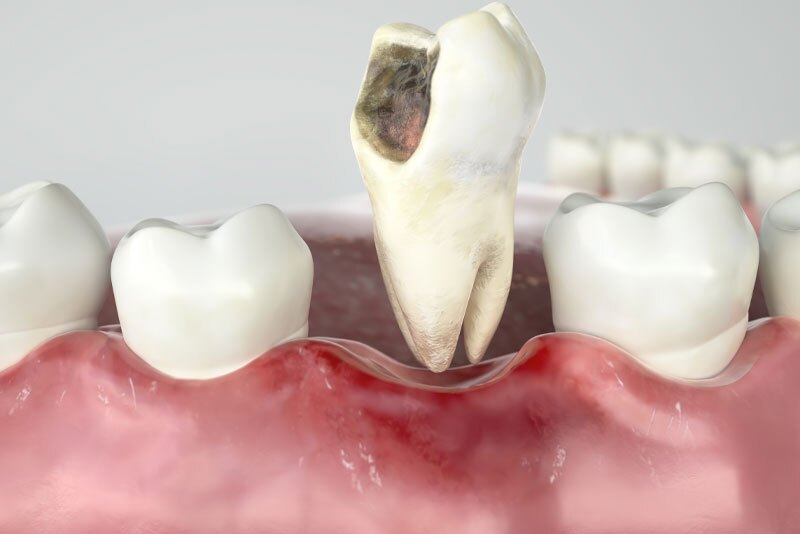

The decision to perform an extraction is typically straightforward when a tooth is affected by significant decay, severe periodontal disease, or a fracture. Digital X-rays are used to analyze the underlying structures and determine if the tooth can be saved. If there is a pulp infection without a tooth fracture, root canal therapy is a highly successful method for preventing extraction.

Extraction of normal teeth may be required for orthodontics, full mouth dental implants, or when a primary tooth hasn't fallen out and is preventing a permanent tooth from erupting. At Kari Mann Dental Studio in Cape Coral, our goal is always to save natural teeth. However, if conservative treatment is ineffective, extraction may be necessary. Removing a damaged or abscessed tooth can prevent more serious issues from impacting other teeth, your oral health, and even your physical health.

We always strive to preserve a natural tooth. However, if the tooth is untreatable, the best way to relieve your toothache and preserve your health may be a tooth extraction.